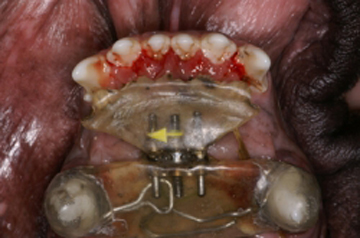

La ortodoncia es una especialidad que requiere de una capacitación muy profunda ya que la boca tiene un hueso, la mandíbula, la cual se mueve y se desplaza en movimientos de rotación y traslación tanto unilaterales como bilaterales. Cuando el médico tratante realiza un tratamiento de ortodoncia, debe saber que puede provocar una serie de trastornos que pueden dañar irremediablemente la buena oclusión del paciente al provocar interferencias oclusales y puntos prematuros de contacto. También es importante conocer cuanta es la presión que debe ejercerse por diente ya que una fuerza exagerada puede provocar la resorción de la raíz del diente provocando que la pieza dental se pierda después de realizar el tratamiento ortodóntico. Es por eso que mover dientes implica tener conocimientos de oclusión y de biomecánica. La ortodoncia provoca un estado inflamatorio controlado en donde se ejercen fuerzas de presión y tensión sobre los dientes y estructuras adyacentes por medio de elementos fijos rígidos y elásticos como son los bracketts, tornillos, aparatos de acrílico, ligas, elásticos, resortes, etc. Para mover un diente o un conjunto de dientes se requiere que el aparato que realizará este movimiento este anclado a estructuras dentales con una mayor cantidad de superficie radicular para que no se mueva al producir el efecto de presión, y provocando consecuentemente el movimiento de los dientes que tienen una menor superficie de contacto radicular al hueso, por lo que el diseño de los aparatos a colocar en la boca del paciente requiere de la toma de buenos modelos de yeso de trabajo y de un diseño adecuado del aparato adaptado a cada paciente dependiendo de varios factores tales como tamaño del paciente, edad, tipo de mordida, tipo craneal, etc.

La posición del aparato en los dientes de la boca y de las estructuras como bracketts a diferentes niveles de la corona del diente a mover, provocan un vector en la dirección del movimiento dental al ser activadas por una fuerza. Esta situación se presenta por la posición y largo de la raíz incrustada dentro del hueso del diente a mover, ya que al ejercer la presión del elástico en una posición de la corona se provoca un movimiento de inclinación en la raíz del diente en donde el centro de equilibrio de las fuerza en la raíz denominada fulcro, es el centro de rotación del movimiento. Este movimiento no se convierte solo en un movimiento bidimensional, sino que la transmisión de vectores de fuerza ocasiona el movimiento tridimensional. El hecho de cambiar el punto donde se coloca el brackett en el diente, ejercerá un vector distinto que traerá como resultado un movimiento completamente diferente. El tejido que recibe todo el peso del tratamiento es el tejido óseo que gracias a su fisiología permite realizar movimientos dentales por sus mecanismos de resorción ósea en donde se aplica la presión y aposición ósea en donde se aplica la tensión. Este proceso inflamatorio controlado no puede permitir excesos en la fuerza de presión de la raíz al tejido óseo alveolar ya que esto provoca una zona isquémica con el deficiente intercambio sanguíneo entre células con el consecuente daño tisular (resorción radicular, necrosis ósea, etc.). Es por esto que deben establecerse las fuerzas que se aplican en los dientes y su frecuencia para lograr el éxito del tratamiento en el menor tiempo posible y con el menor daño tisular. Los tratamientos de ortodoncia pueden ser preventivos, interceptivos y correctivos.